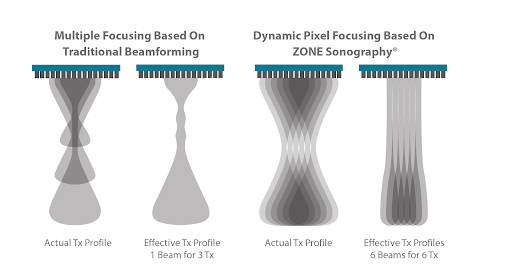

Динамическая фокусировка пикселей

Технология динамической фокусировки пикселей системы Resona 6 позволяет достичь непревзойденной однородности изображения на всей области сканирования. Теперь, обследуя пациента, не нужно настраивать фокусное расстояние для получения однородного изображения.